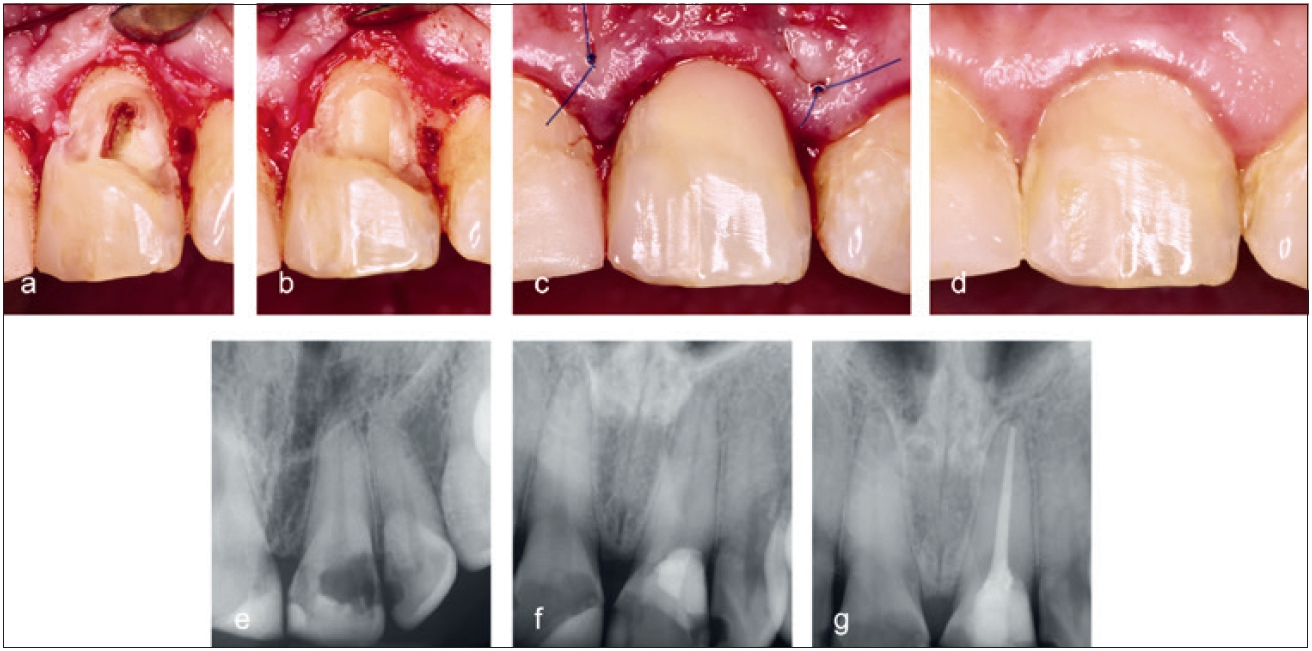

Liegt der Defekt weitgehend supraosseär und ist ein ungehinderter Zugang möglich, kann der meist weichgewebige Inhalt von außen entfernt werden (Abb. 14). Falls das Resorptionsgewebe nicht vollständig erreichbar ist, können 90%ige Trichloressigsäure (TCA) oder 3- bis 5%iges Natriumhypochlorit (NaOCl) angewendet werden, um eine Blutstillung zu erreichen und das Restgewebe aufzulösen [21,32] (Abb. 15).

Dr. Widbiller

Die Restauration der zervikalen Kavität erfolgt in Bereichen, die der Mundhöhle zugängig sind, mit Kompositen in Adhäsivtechnik (Abb. 14 und 15). Liegt der Defekt in unmittelbarer Nähe zur vitalen Zahnpulpa oder wurde das Pulpakavum eröffnet, sollten vitalerhaltende Maßnahmen im Sinne einer indirekten bzw. direkten Überkappung vorgenommen werden. Bereiche, die direkt an Knochen grenzen, müssen mit hydraulischen Kalziumsilikatzementen versorgt werden. Hierzu eignen sich Mineraltrioxidaggregat (z.B. ProRoot MTA, Dentsply DeTrey GmbH, Konstanz) oder modifizierte bioaktive Zemente (z.B. Biodentine, Septodont GmbH, Niederkassel). Diese härten in Anwesenheit von Feuchtigkeit aus und bieten biologisch günstige Eigenschaften, sodass knöcherne Defekte ausheilen können.